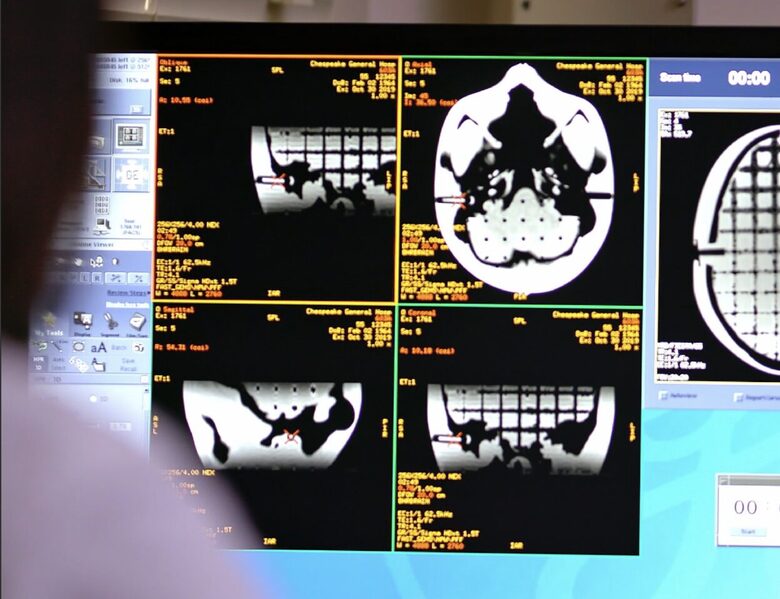

When using MRI images for radiosurgery, it is essential to ensure that the images contain no geometric distortions. Even small deviations can affect radiation dose accuracy and treatment outcomes.

All measurements are performed on-site using your standard MRI sequences. After the evaluation, we provide a detailed MRI distortion analysis report.